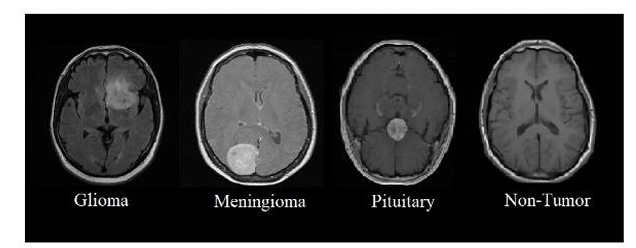

We used the publicly available Brain Tumor Detection and Classification MRI image Kaggle dataset are (https://www.kaggle.com/datasets/sartajbhuvaji/brain-tumor-classification-mri). There are 3264 brain MRI images in dataset which have been labelled as glioma tumor, meningioma tumor, no tumor and pituitary tumor. Including the number of these brain MRI images are 926 images of glioma, 937 images of meningioma, 500 images of no tumor and 901 images of pituitary tumor. The images were processed, they were divided into a training and validation set using an 80%-20% split respectively. Depending on their types and grades, brain tumor can vary in terms of size, location and shape.

fig, ax = plt.subplots(1,4, figsize=(20,20)) k = 0 for i in range(0,4): if i==0: idx=0 elif i==1: idx=827 elif i==2: idx=1649 else: idx=2045 ax[k].imshow(X_train[idx]) ax[k].set_title(Y_train[idx]) ax[k].axis('off') k+=1